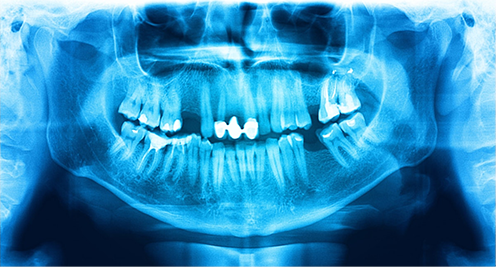

review oncology plan, imaging and oral history.

fluoride trays, periodontal therapy, planned extractions if indicated.